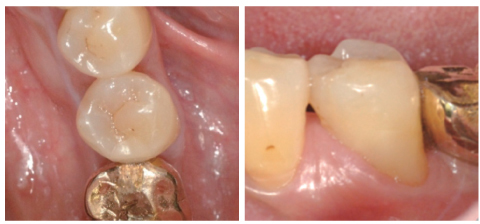

Figure 1

Preoperative periapical view and clinical photograph. (a) Periapical radiolucency on #35; (b) Cervical abrasion.

Figure 1 Preoperative periapical view and clinical photograph. (a) Periapical radiolucency on #35; (b) Cervical abrasion.